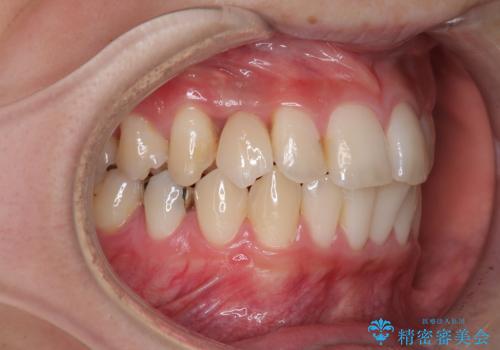

[ 乳歯の残存 ] 前歯のインプラント治療